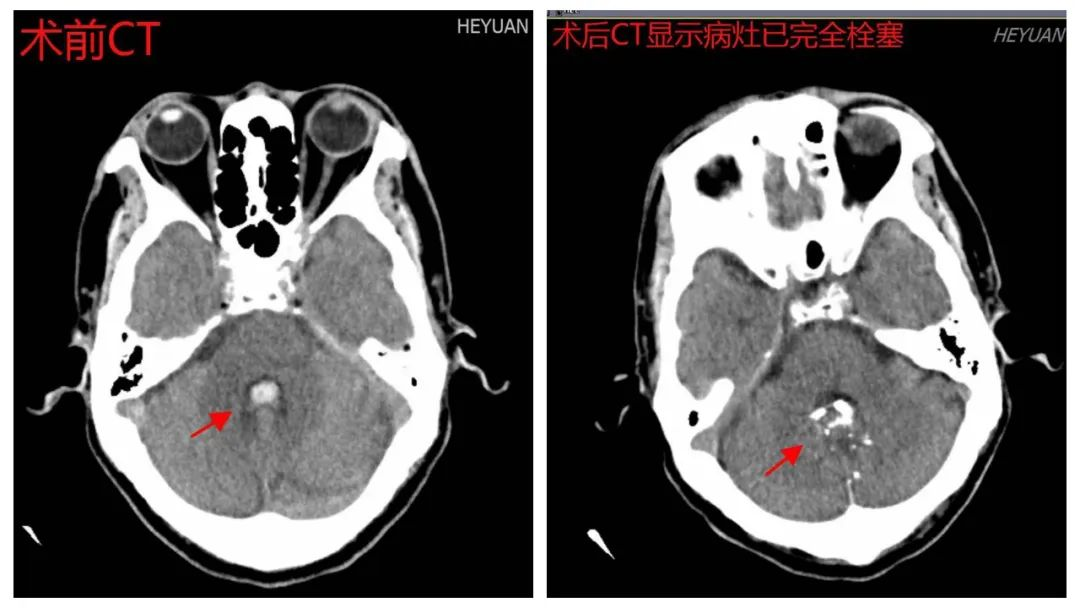

7月2日下午,经过充分术前准备、讨论,多学科会诊,陈光忠教授指导神经外科二区刘胜初主任医师团队为患者成功进行了小脑蚓部动静脉畸形(b-AVMs)合并动静脉瘘(AVF)血管内介入栓塞治疗,手术治疗时间仅20分钟,达到完全栓塞,没有发生并发症。

术前、术后CT影像对比